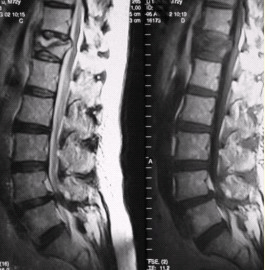

患者男,70岁,因肝癌入院,准备行肝移植手术。住院期间因腰扭伤而腰痛,故行腰椎MRI检查(如下图)。 FSK_MN1_43.gif

关于压缩性骨折椎体的特点,描述正确的是

观察上面的影像后,你认为正确的是

正确的诊断为

鉴别椎体良、恶性压缩性骨折,支持良性病变的征象有